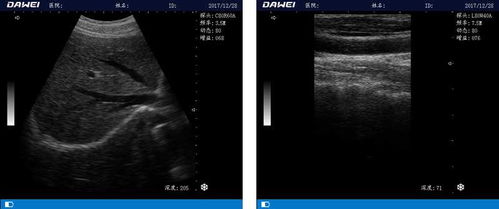

高清直播系统可以将B超设备采集到的图像实时传输到医生工作站,医生可以远程观察患者的实时图像,从而提高诊断的准确性和效率。此外,高清直播系统还可以实现多台B超设备之间的图像共享,方便医生进行会诊。

高清直播系统可以实现B超图像的远程传输,医生可以远程为患者进行诊断,为偏远地区的患者提供便捷的医疗服务。同时,高清直播系统还可以实现远程手术指导,提高手术成功率。

高清直播系统可以将B超操作过程实时传输到教室,为学生提供直观的教学体验。此外,教师还可以通过高清直播系统进行远程授课,提高教学质量。